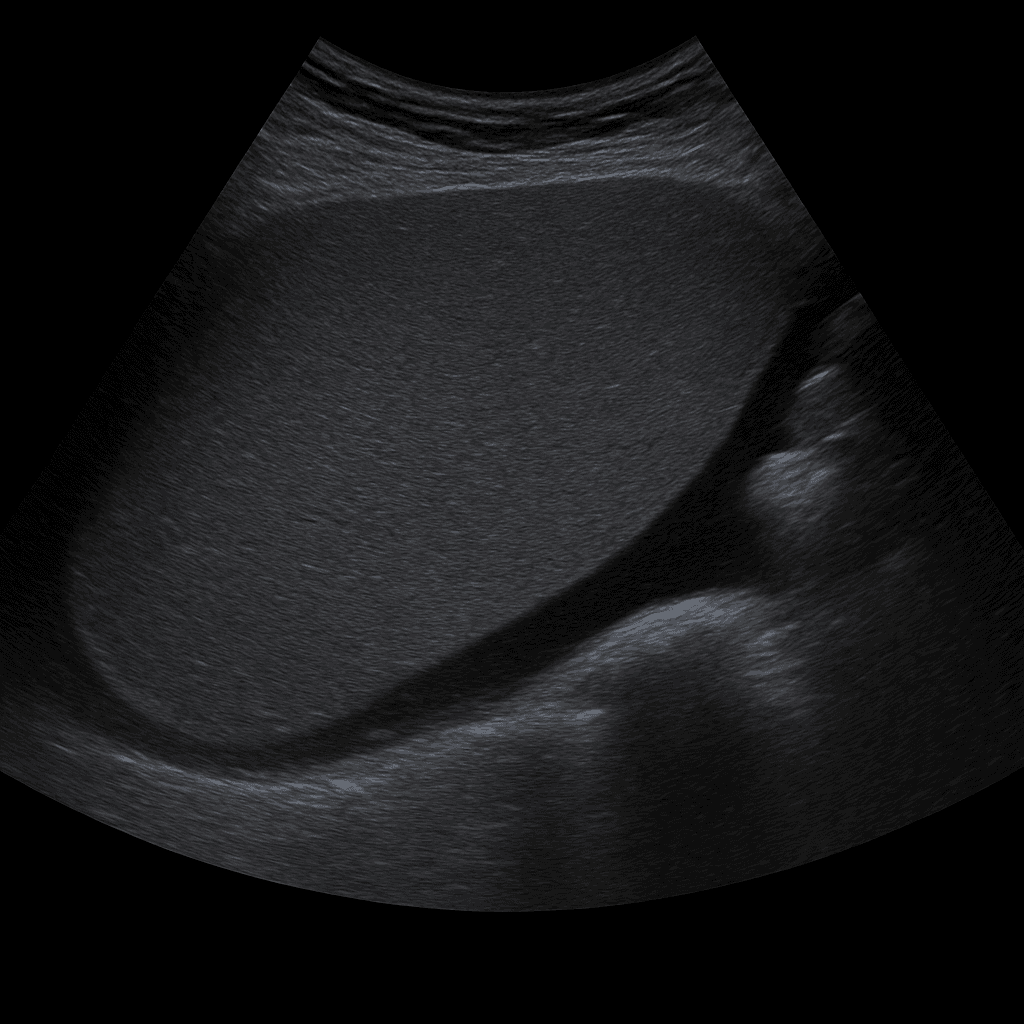

Ett ultraljud av mjälten används för att undersöka mjältens storlek, form, vävnadsstruktur och blodflöde. Undersökningen utförs av specialistläkare inom radiologi och ger detaljerade bilder i realtid som kan visa tecken på förstoring, cystor, infarkter eller andra förändringar. Ultraljud mjälte används ofta för att utreda orsaken till buksmärta, infektion, anemi, misstänkt förstorad mjälte (splenomegali) eller som del av en utredning av lever- och blodsjukdomar.

Undersökningen utförs medan du ligger på rygg eller på höger sida. En gel appliceras på huden och läkaren för ultraljudsproben över området under vänster revbensbåge. Mjälten avbildas i olika vinklar för att bedöma storlek, vävnad och kärlflöde. Vid behov kan även lever och njure på vänster sida granskas som jämförelse.